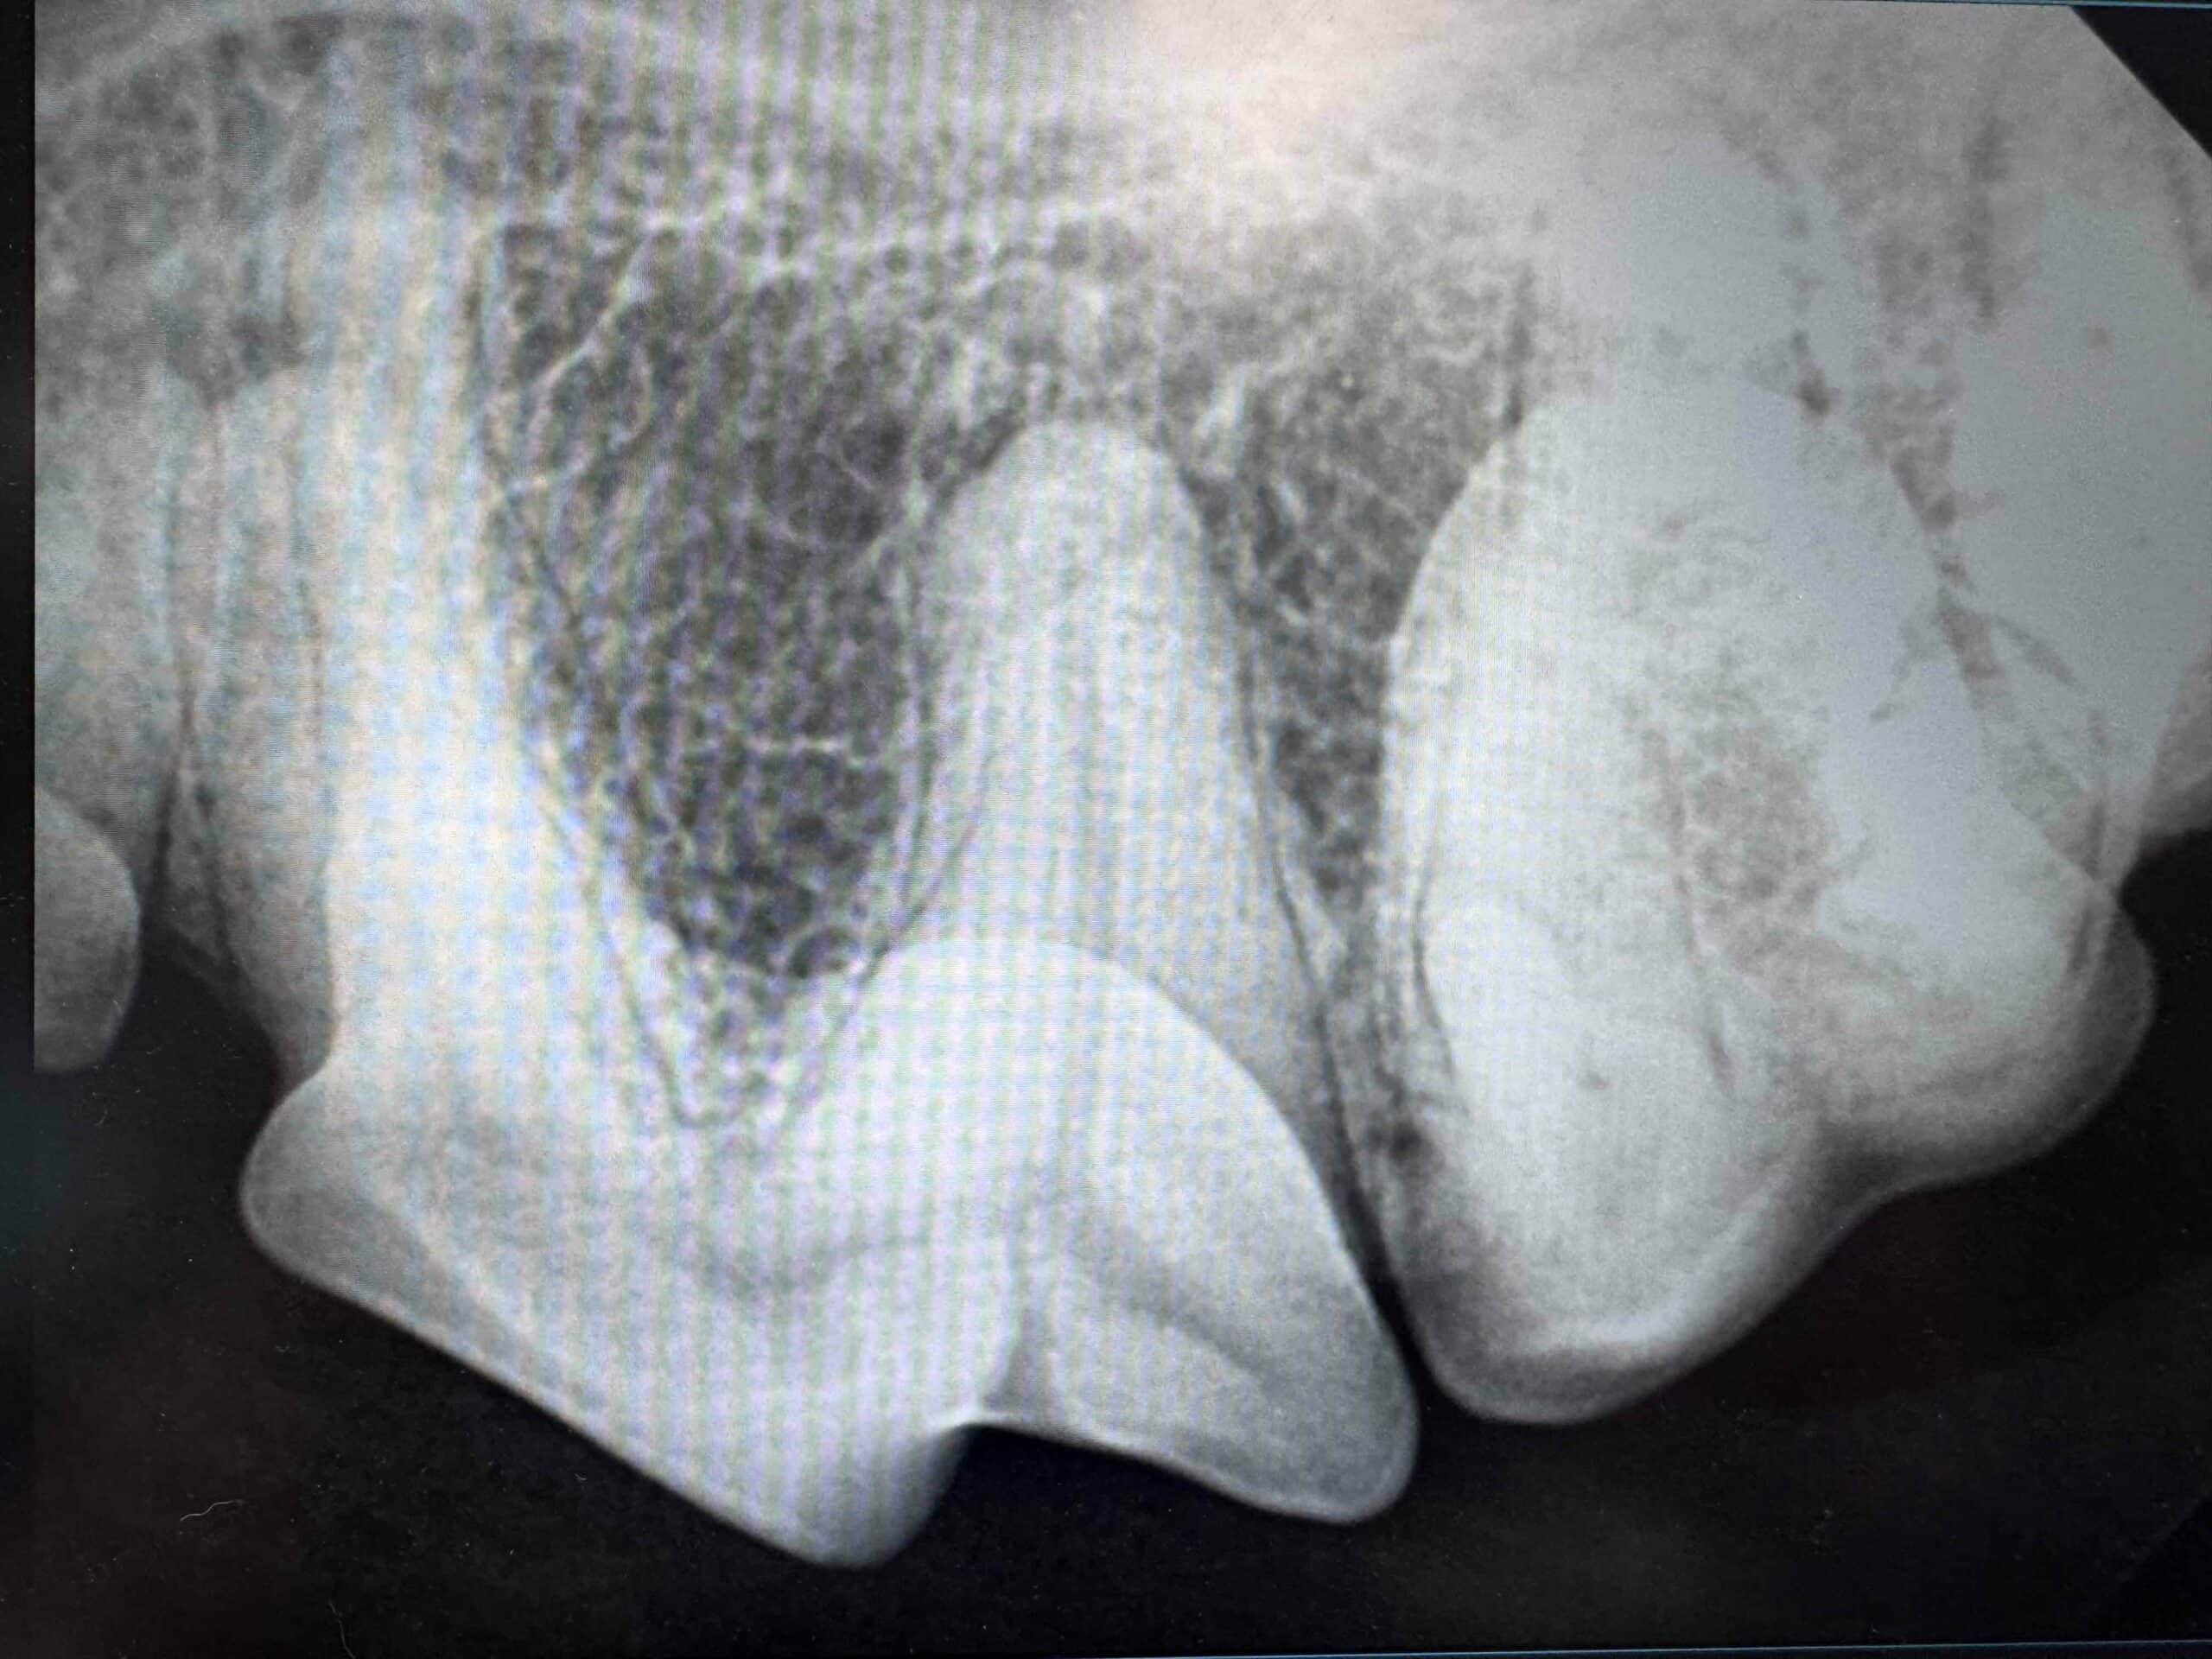

Digital Dental X-rays

High-resolution radiographs allow the team to see below the gumline, detecting hidden problems such as abscesses, bone loss, or fractured roots.